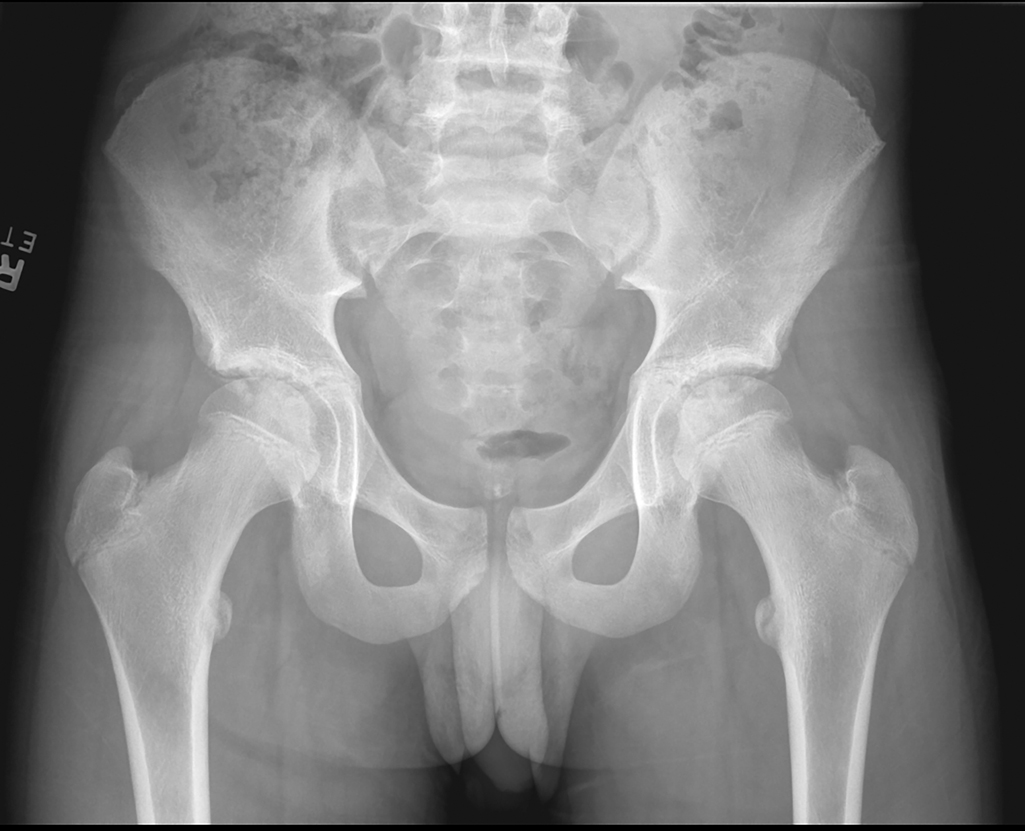

Рентгенография бедренной кости выявляет изменения только на поздних стадиях — очаги остеолиза, периостальную реакцию и секвестры и направлена на выявление прямых признаков деструктивного воспалительного процесса, затрагивающего метафизарные и эпифизарные отделы бедренной кости. Исследование проводится в прямой и боковой проекциях в режиме прицельной рентгенографии с фокусом на верхнюю треть бедренной кости.

Рентген выявляет следующие анатомические признаки:

Остеомиелит проксимального эпифиза бедренной кости:

- Очаговая остеолизация в области шейки, головки или вертелов с нечёткими размытыми краями.

- Периостальная реакция в виде наслоений по наружной поверхности шейки или вертелов.

- Формирование секвестров в виде изолированных плотных участков на фоне деструкции.

- Субхондральная деструкция с вовлечением суставной поверхности головки бедра.

- Нарушение конфигурации вертелов за счёт остеосклероза и деформации.

- Сужение тазобедренной суставной щели на фоне артропатии.

- Разрушение кортикального слоя шейки бедра с прерывистостью и утратой гладкости.

- Деформация проксимального отдела и асимметрия в сравнении с противоположной стороной.

- Плотный склеротический вал при хроническом течении с секвестральной полостью.

- Широкая мягкотканная тень в проекции бедра с признаками воспалительного инфильтрата.

Рентгенографическое исследование позволяет детально визуализировать следующие диагностические параметры:

- Локализация и протяжённость очага воспаления с возможностью точной оценки поражённых анатомических отделов кости.

- Форма и степень разрушения кортикального слоя, включая наличие прорыва наружного костного контура и формирования свищевого хода.

- Характер субпериостальных изменений, таких как наслоения, утолщение и отслоение надкостницы, позволяющих оценить фазу процесса.

- Наличие секвестра и его положение внутри зоны деструкции, а также объём реактивного остеосклероза в окружающей ткани.

- Степень вовлечения костномозгового пространства с визуализацией склерозированных участков и расширением канала.

Рентгенологическое обследование имеет ряд ограничений, и с его помощью не всегда удаётся точно визуализировать следующие аспекты:

- Начальные стадии воспалительного процесса без выраженного остеолиза могут протекать без рентгенологических изменений.

- Глубина поражения костномозгового пространства и степень васкулярной реакции в очаге воспаления недоступны для оценки при рентгенографии.

- Ранние изменения в окружающих мягких тканях, включая инфильтрацию и отёк, не визуализируются на стандартных рентгенограммах.

- Переход воспаления на тазобедренный сустав с формированием артрита не всегда выявляется на раннем этапе без дополнительных проекций.

- Присутствует лучевая нагрузка: при выполнении рентгенографии проксимального отдела бедренной кости в прямой и боковой проекциях с применением прицельной съёмки поражённого сегмента суммарная эффективная доза составляет от 0,4 до 0,8 мЗв.